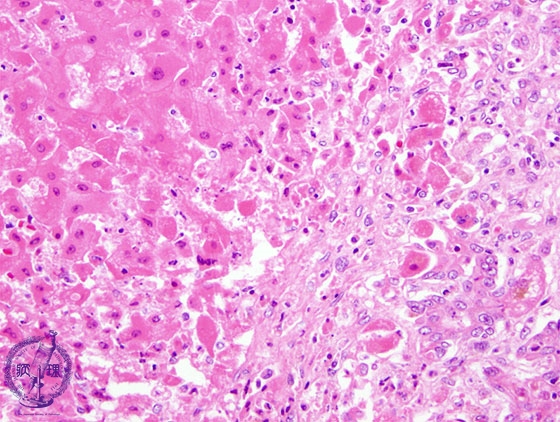

- ★(3)Fulminant hepatitis

Microscopic image (HE stain, high power): There is an interface between necrotic (left of the dotted line) and non-necrotic areas; the necrotic hepatocytes are swollen and more eosinophilic.